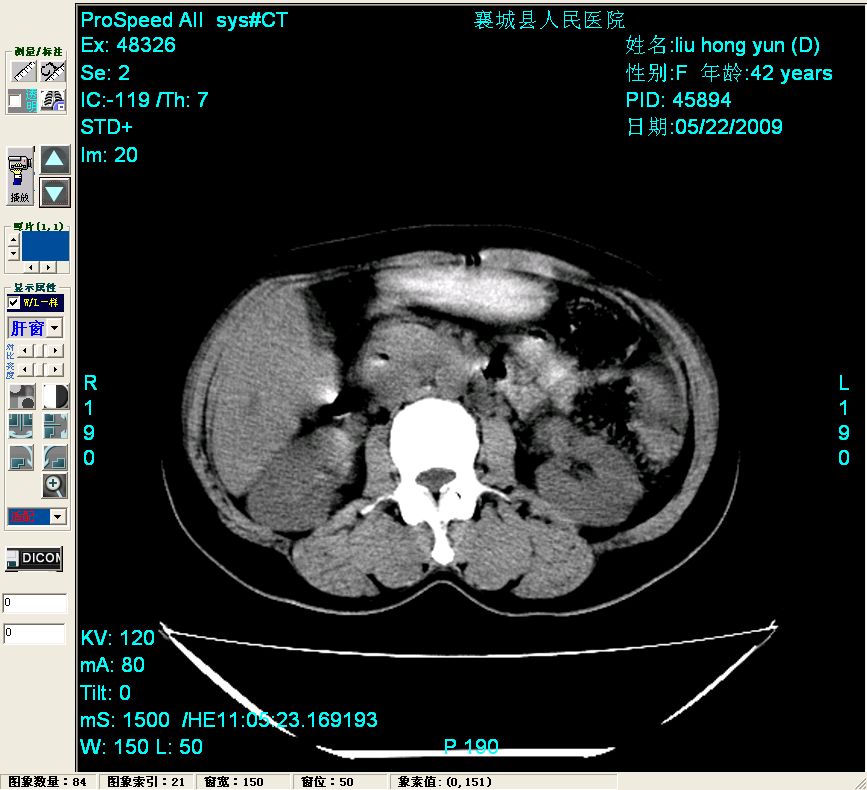

增强:

增强动脉期前述低密度区轻度早其强化,门脉期强化程度显著增高,延期扫描强化程度下降,但仍为相对高密度影

胰头部见结节状高密度影,其前方略可分辨扩强胆部管,平扫到增强始终有,但现在尚难与胃肠造影剂鉴别.

结合病史考虑,1现在引起黄疸体征的原因应该是胆总管胰段结石阻塞,建议局部胃肠造影剂排空后复查.

胆总管末端结石伴肝内胆管扩张合并结石!另:不除外合并胆系感染!

考虑:1、胆道结石伴肝内胆管扩张、积气;胆系感染!2、从平扫、增强片来看,不存在胆管肿瘤征象;3、提介建议:作为影像医师,在做一项检查之前应先熟悉临床医生的目的,象这个病例,检查前就不应喝高密度造影剂,而应充分喝好水就可,要不适得其反,反而较难判断胆总管下段是否有结石。